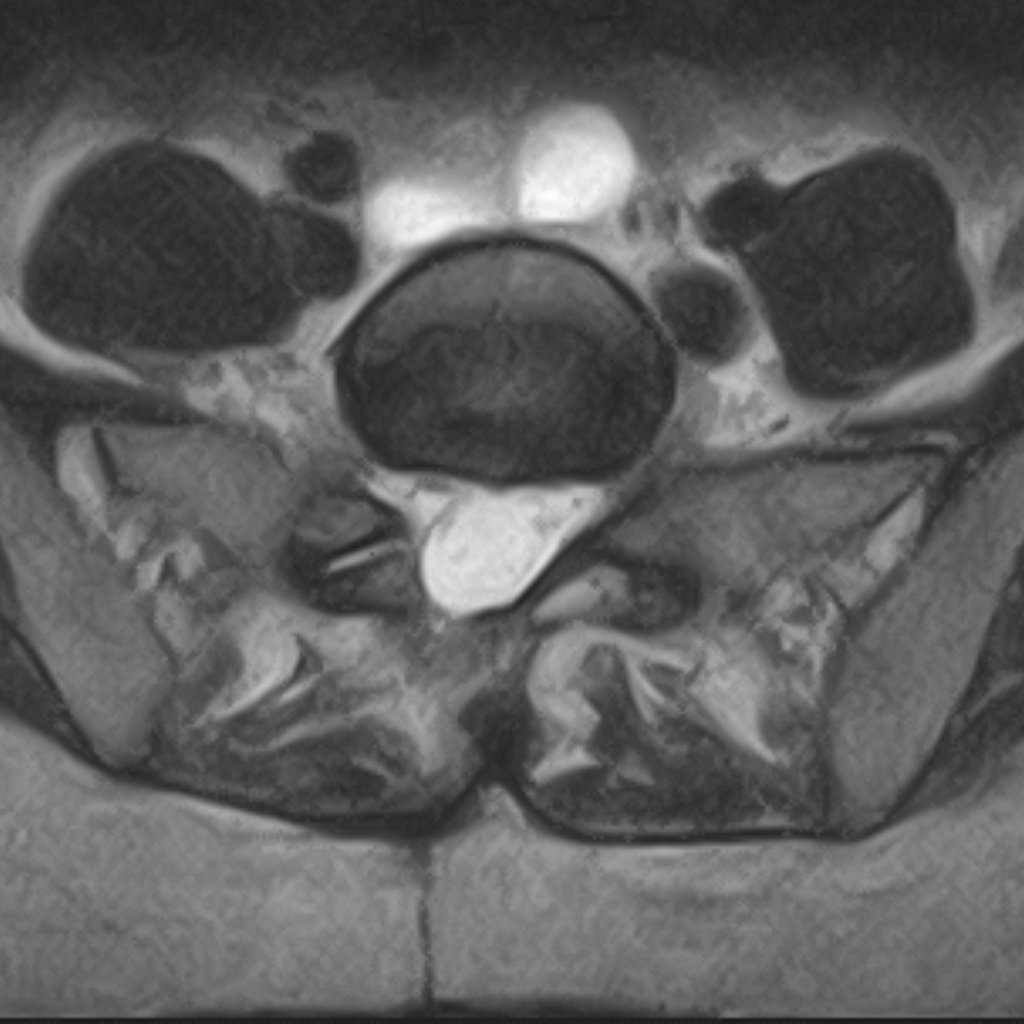

Axiális MRI felvétel — lumbális porckorongsérv

MRI: lumbar disc herniation — disc material compressing the nerve root

Lumbar disc herniation typically causes radiating pain into the leg, numbness, and muscle weakness. MRI is required for accurate diagnosis.